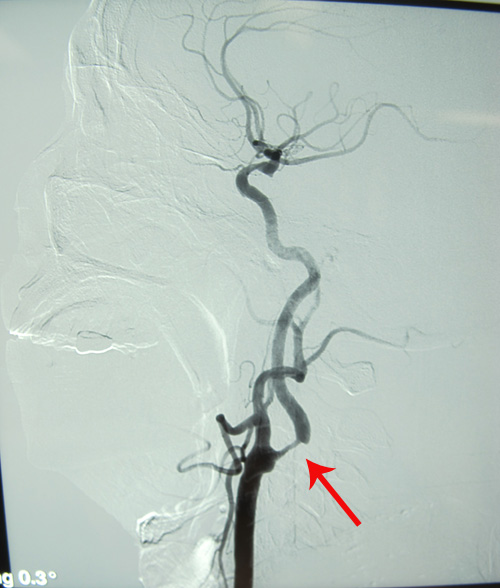

DSA(2011-3-21,人民医院):双侧颈内动脉起始部及右颈内动脉虹吸段及右侧大脑后、小脑上动脉起始段多发动脉硬化斑块形成,伴不同程度的管腔狭窄。

该患者左侧颈内动脉环周低回声斑,管腔狭窄约75%-80%,症状明显,且有高血压及糖尿病史,符合颈动脉内膜剥脱术手术指征。于2011年3月25日,由协作组张勤奕教授顺利为其实施了左侧颈动脉内膜剥脱术。